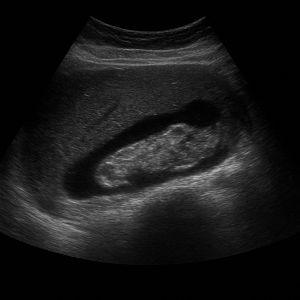

방광과 전립선(남성) 또는 자궁·난소(여성)

- 남성은 전립선 상태나 비대, 염증, 혹은 종양 여부를 확인할 수 있어요.

- 여성의 경우 자궁이나 난소 상태를 살펴보며, 난소 낭종, 자궁 근종, 혹은 다른 병변 의심도 파악할 수 있답니다.

또한 방광 상태, 예를 들어 잔뇨나 방광벽 상태도 초음파로 확인 가능해요.